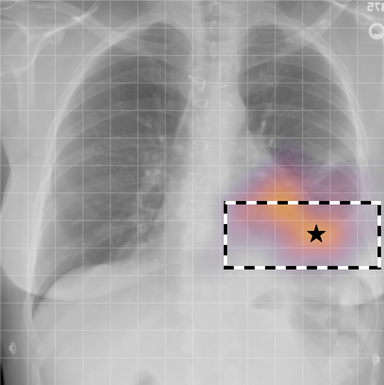

| (1) |

for , where denotes 2D sinusoidal positional encodings [12] and is its temporal counterpart, which is learnt (Fig. 2) [4]. The layer-normalised () [6] output of the final transformer encoder block is an ‘aggregated’ representation of patch-level progression information anchored on the current image. Figure 3 shows attention roll-out [1] applied to after pre-training, showing how the prior image contributes to the fused representation. Figure A.5 further highlights the robustness to variations in pose underlining that registration is not necessary for this encoder.

A.3 Self-attention visualisation

In Figure A.3, we show examples of self-attention rollout [1] maps for pleural effusion and consolidation, including radiologist-annotated bounding boxes surrounding the corresponding pathology in each prior and current image.

To model the attention flow through the transformer encoder block, we first average each attention weight matrix across all heads, subsequently we multiply the matrices between every two layers. For every block we add the identity matrix in order to model the residual connections. Last, we only keep the top 10 of attention weights per block to reduce noise in the final rollout map. In contrast to [21], we do not visualize the rollout map with respect to a [CLS] token. Instead, we choose a reference image patch from the center of the radiologist-annotated bounding boxes, marked with in Figure A.3.

We find that the rollout maps in Figure A.3 are in good agreement with radiologist-annotated bounding boxes, i.e., the reference patch attends to other patches within the bounding boxes in the prior and current image. In addition, we find that BioViL-T is robust to pose variations, e.g., in Figure A.3 (a) we show that despite the vertical shift between prior and current image, the reference patch attends to the correct image patches in the prior image.

To further assess the robustness of BioViL-T against pose variations between prior and current images, we performed multiple rotations to the prior image within a pair and computed rollout maps from the same reference patch in the current image. Figure A.5 shows that BioViL-T consistently attends to the corresponding anatomical region independently of the spatial transformation applied, demonstrating that registration is not needed.